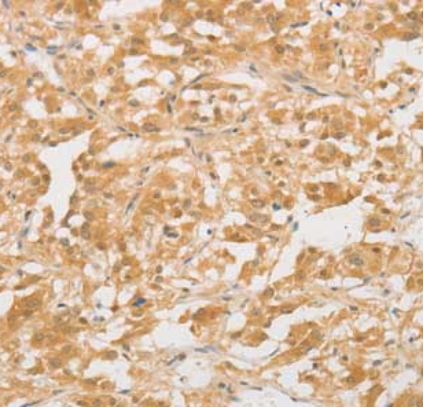

CD24 is a double-stranded glycosylphosphatidylphosphatidylinositol (GPI) glycoprotein that is expressed at multiple stages of B-cell development, beginning with pre-B cells in the bone marrow and ending with a positive immunoglobulin B-cell surface in differentiated mature B cells. Plasma cells show minimal or no expression.CD24 can also be used as a marker for the B-cell lineage of acute lymphoblastic leukemia, and B-cell non-Hodgkin's lymphoma.

CD24 Antibody Reagent binds specifically to the CD24 molecular antigen. Immunohistochemistry kits containing CD24 Antibody Reagent are indicated for the precise diagnosis of B-cell tumors (e.g., Chronic Lymphocytic Leukemia/CLL) and certain solid tumors (e.g., breast cancer, ovarian cancer).